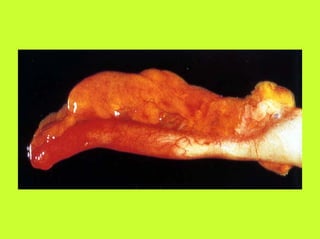

PERFORATIONS

JEJUNO-ILEALES

- ANSE SPHACELEE

- Entérite aigue nécrosante

- Infarctus mésentérique

- Strangulations (volvulus ou bride)

PERFORATIONS JEJUNO-ILEALES - ANSE SPHACELEE - Entérite aigue nécrosante - Infarctus mésentérique - Strangulations (volvulus ou bride) - TRAUMATISMES : Perforation méconnue (plaie ou contusion) - LESIONS INFLAMMATOIRES - Tuberculose, Crohn - Iléite non spécifique - Typhoide - TYPHOIDE - HODGKIN, LYMPHOME NON HODGKINIEN - AUTRES : péritonite noueuse, diverticules, Comprimés de KCL, radiolésions, tumeurs du grêle